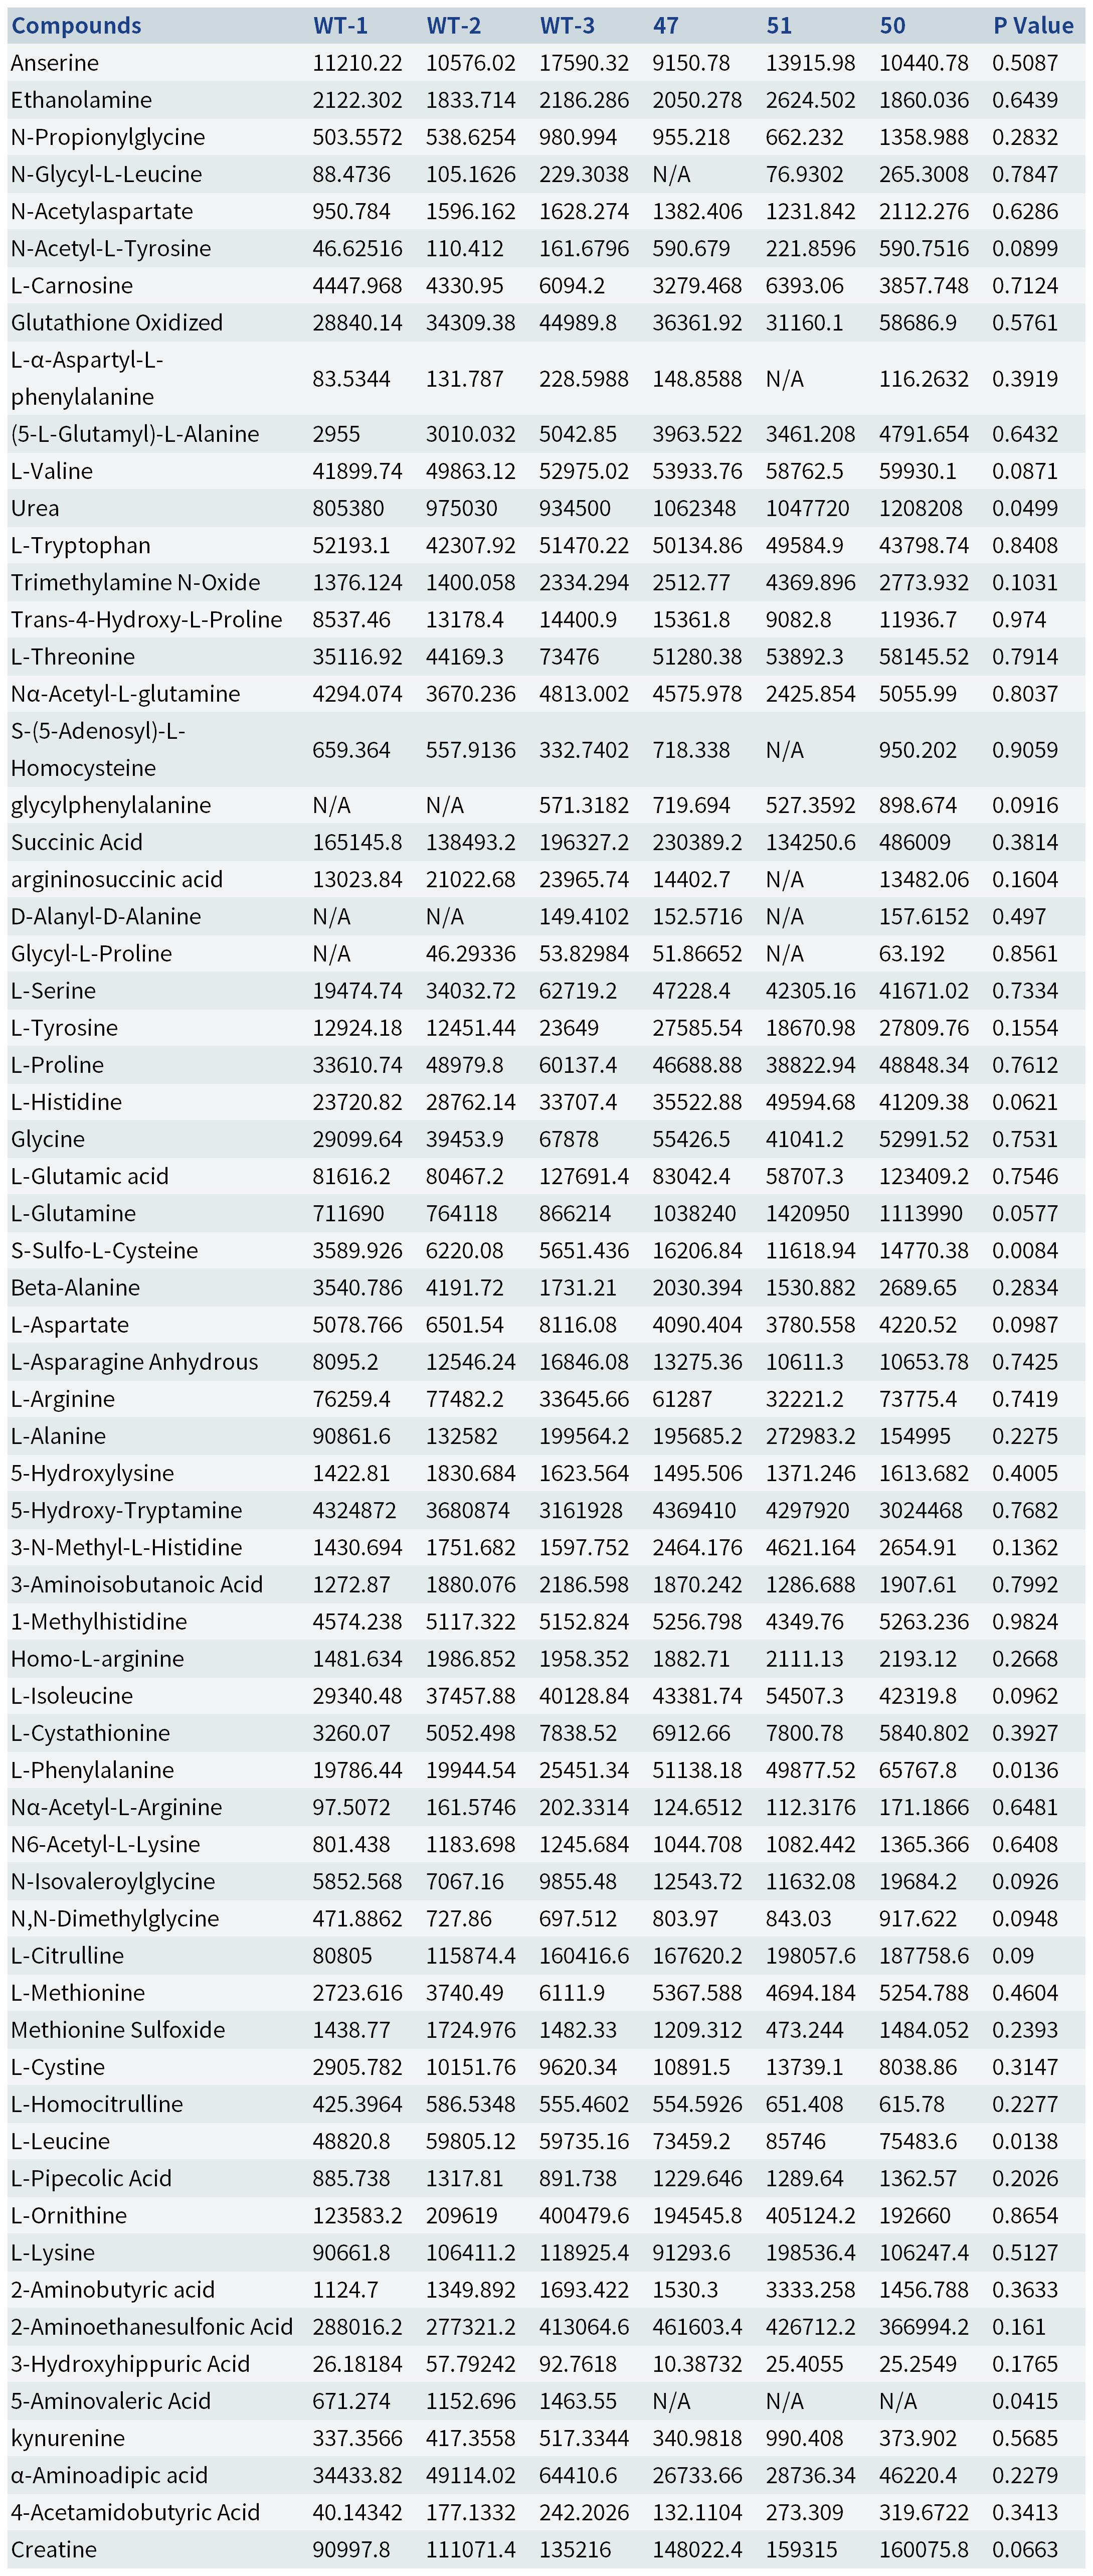

Table1. Detection of blood serum concentrations of the metabolites in Pah-R261Q mice